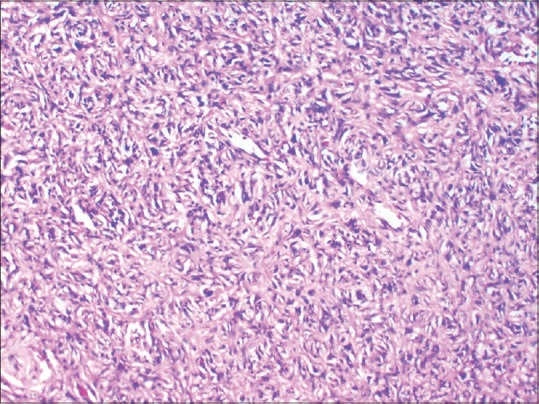

Figure 4.

Spindle cells some showing storiform pattern (H and E, ×400)

A 63-year-old woman, a known diabetic, presented to the dermatology department with a slowly progressive lesion on the back since 26 years. The lesion was initially asymptomatic, but she had recently developed pain and pruritus over it. There was no preceding episode of trauma. Examination revealed a huge, nodulo-ulcerative plaque on the left side of the back of approximately 15 cm × 20 cm size, extending to the nape of the neck superiorly, acromial process laterally and medially crossing the midline up to medial border of the right scapula [Figure 1]. An incisional biopsy was obtained from one of the nodules and sent for histopathologic examination. Microscopically, there was an infiltrating lesion located in the deep dermis and subcutaneous tissue, composed of spindle cells arranged in a storiform pattern [Figures 2 and 3]. The cells showed elongated nuclei, fine chromatin and moderate amount of eosinophilic cytoplasm. Many foreign body giant cells with occasional bizarre cells were also seen. Immunohistochemical staining with CD34 markers was negative while there was positivity for CD68 [Figures 4 and 5]. These findings were consistent with the diagnosis of benign fibrous histiocytoma, probably cellular type. The patient was referred to plastic surgery, where she underwent wide local excision with skin grafting. She came for follow-up after 6 months, and there was no tendency for recurrence [Figure 6].